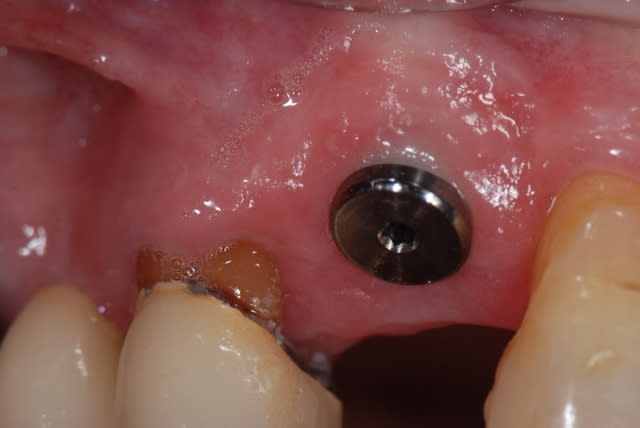

je te propose ce cas que j'ai achevé il y a 2 mois; tu verras que la notion de limite est variable, sauf celle du blocage primaire, d'où cette proposition de mise en esthétique uniquement avec un bon blocage primaire;

j'ai mis du ß TCP sans membrane, j'ai eu une très légère récession gingivale que l'utilisation des TBR Zircone autorise sans soucis avec un sourire non gingival

la pose a été faite 6 mois plus tard

6 mois kx5itc - Eugenol

Pose qmceht - Eugenol

la dernière radio est à 6 mois post op, il y a eu une petite inflammation distale qui m'a fait perdre un peu de hauteur, provoquée par un grain de TCP qui est resté bloqué en surface pendant les vacances cet été; le PBI est revenu à 0 depuis